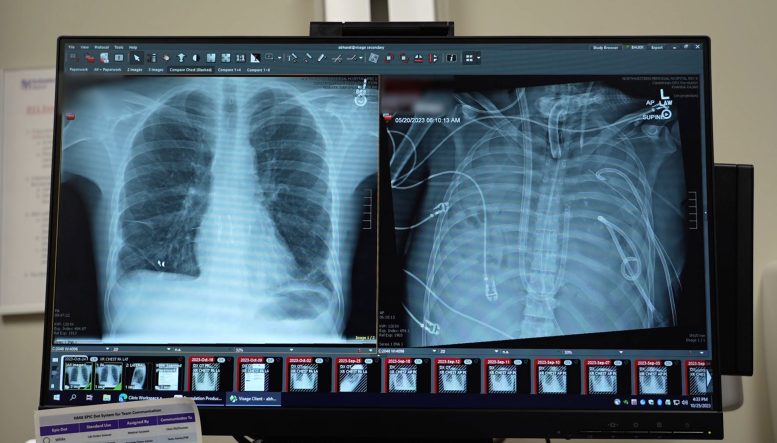

In a study published in the Cell Press journal Med, surgeons detailed how they extracted a patient’s severely infected lungs and relied on a custom-built “artificial lungs” setup to sustain him until donor organs became available. The team describes the strategy as a potential bridge to transplantation for patients who would otherwise die waiting.

To buy that time, Bharat and his colleagues created a system that could temporarily perform the essential tasks of the lungs. The device added oxygen to the blood, cleared out carbon dioxide, and supported circulation so the heart could keep pumping effectively, even in the complete absence of lungs.

After surgeons removed the infected organs, the patient’s health began to rebound. His blood pressure steadied, his other organs started functioning again, and the infection came under control. Two days later, compatible donor lungs were found, and the team carried out a double lung transplant. More than two years after the operation, he is back to his normal routine with strong lung function.